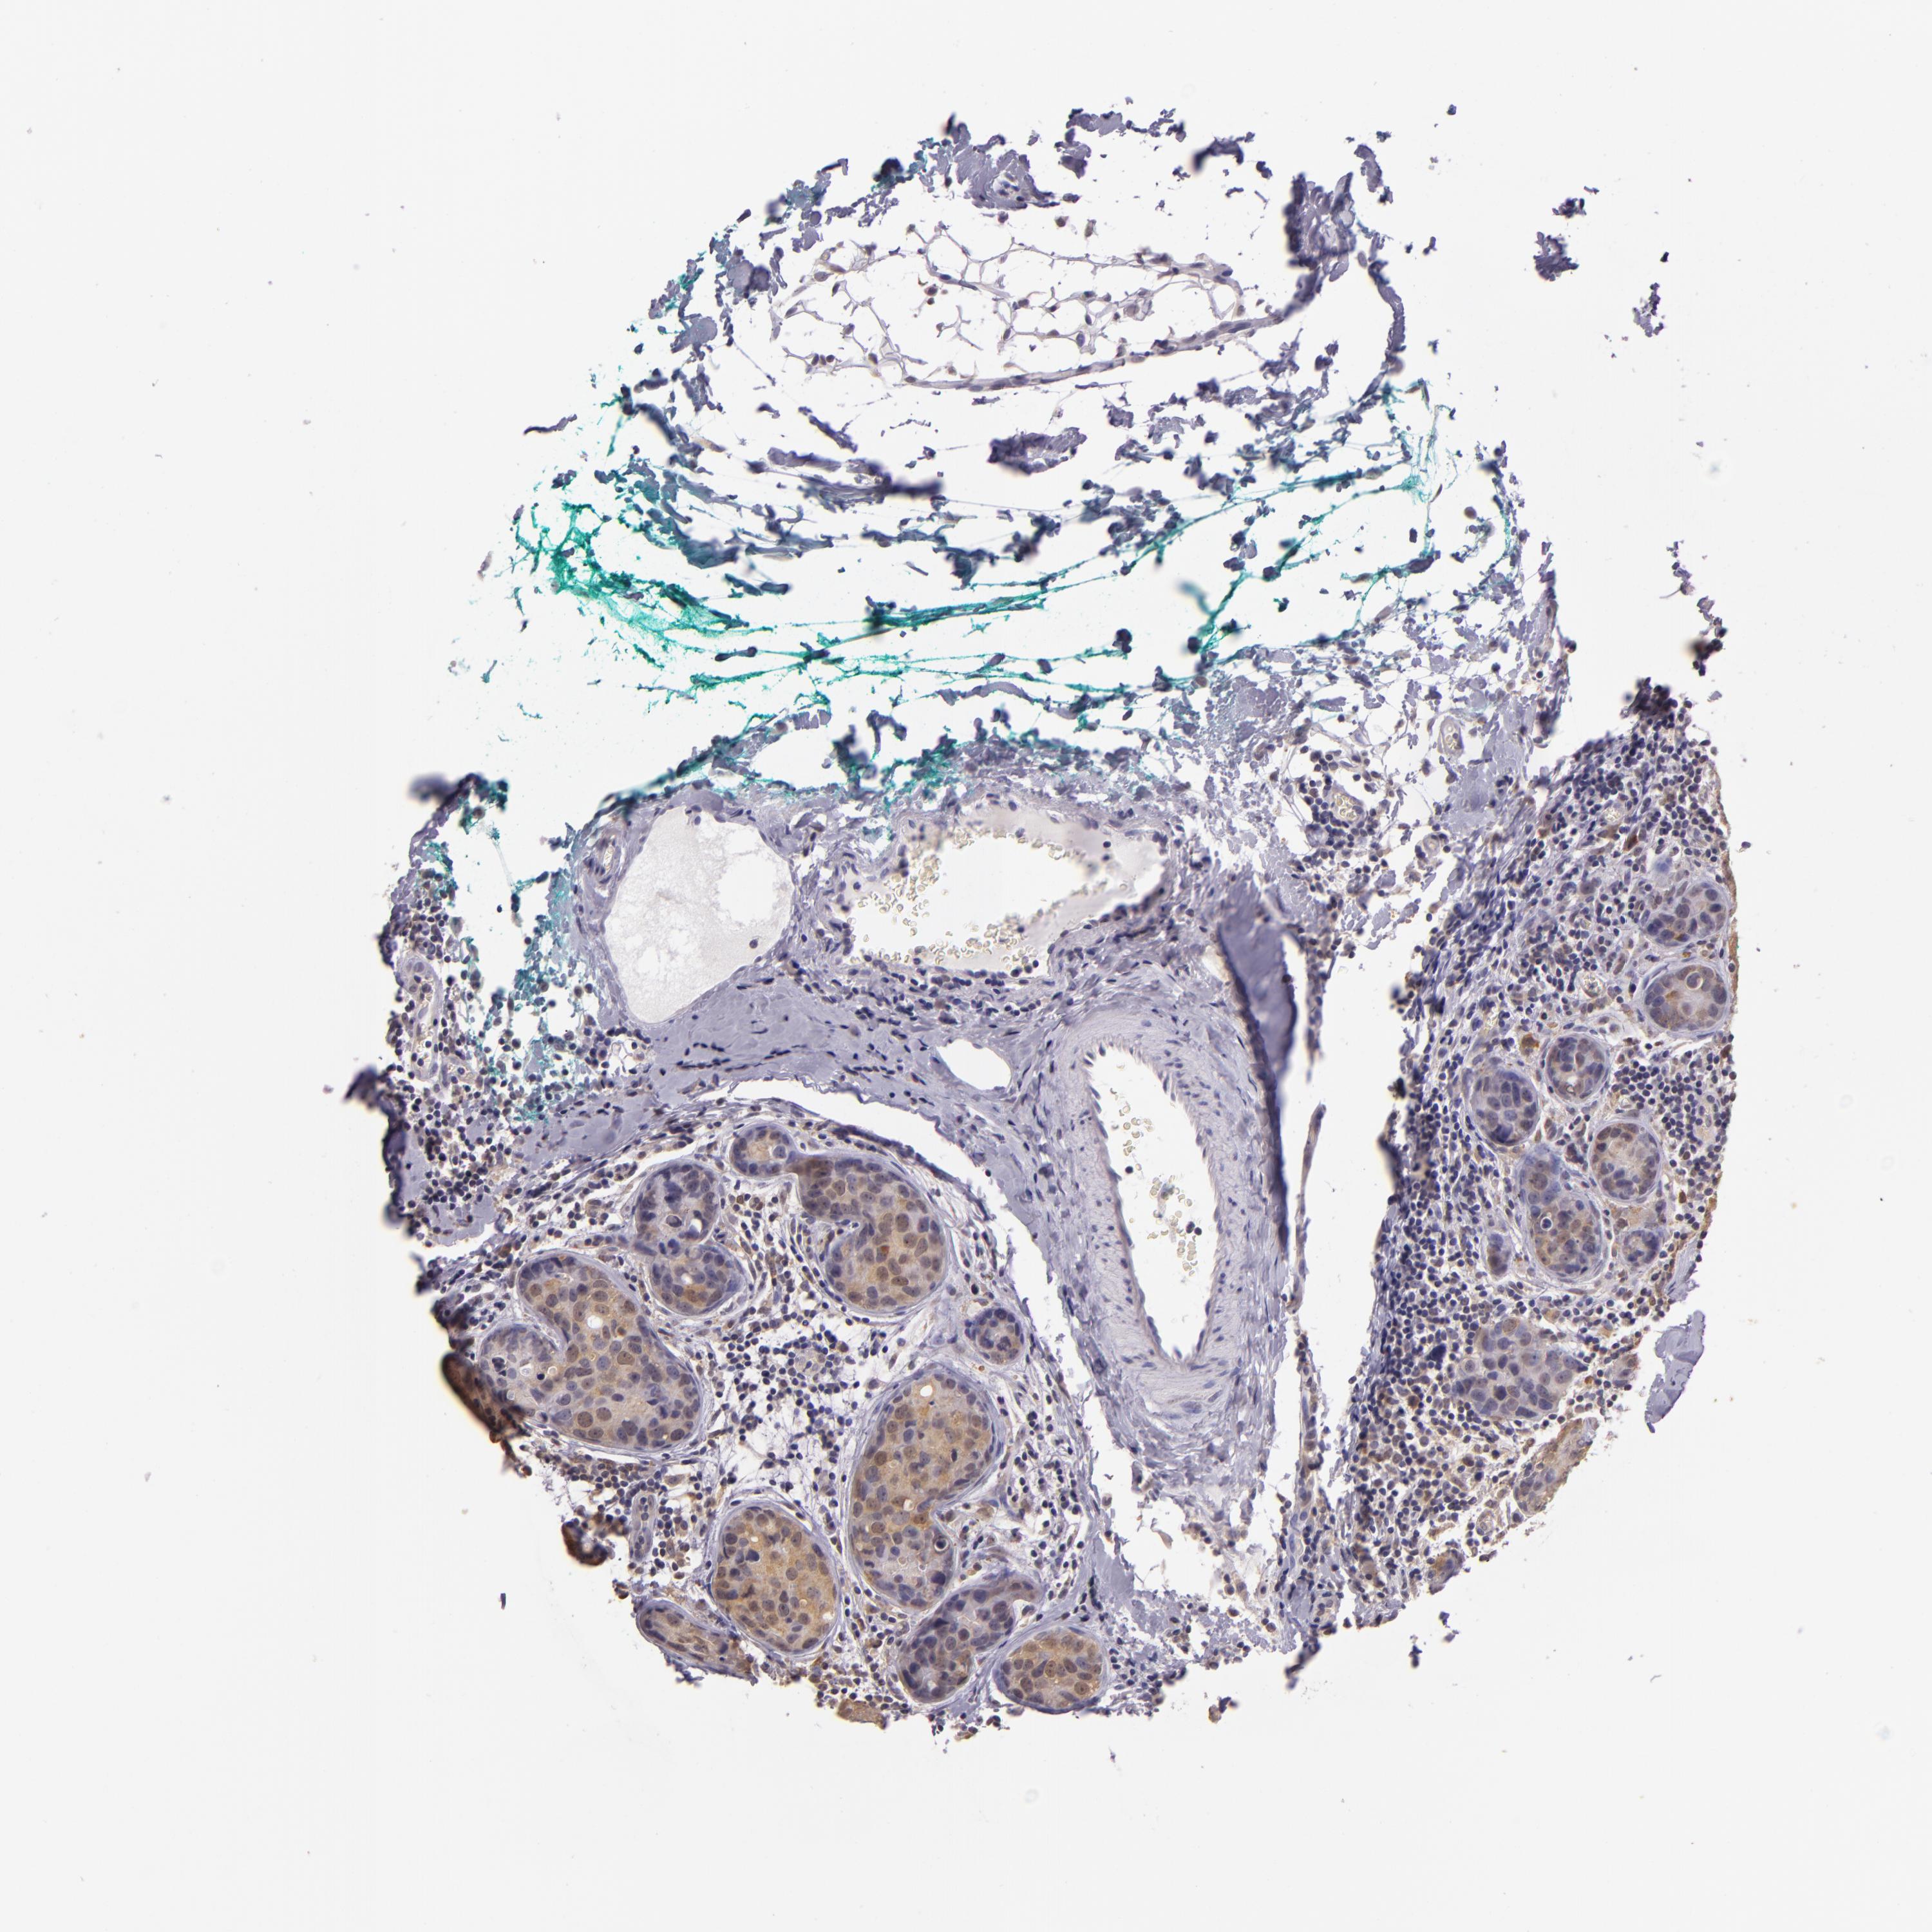

CANCER BREAST CANCER Show tissue menu

BRCA TCGA BRCA VALIDATION PROTEIN EXPRESSION

ANTIBODIES

AND

VALIDATION